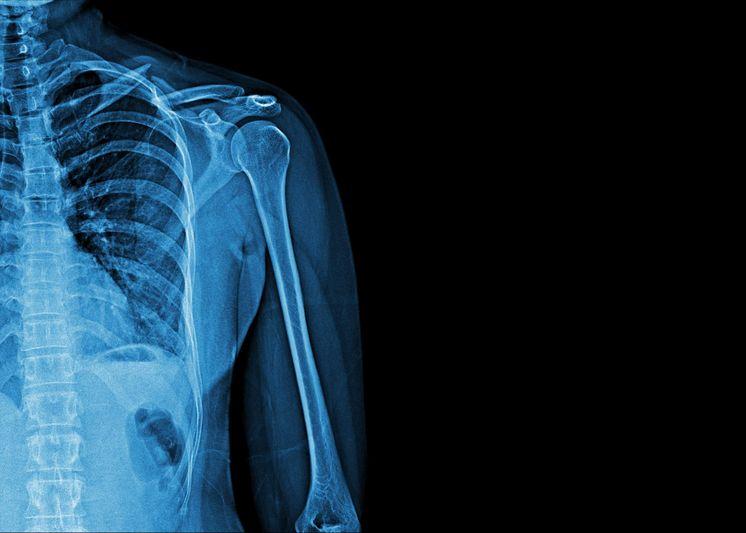

Перелом большого бугорка плечевой кости

Этот вид травм верхнего отдела опорно-двигательной системы встречается намного реже, чем повреждения рук или ключиц. При этом перелом такого типа нередко имеет вторичную природу и сопровождает вывихи плечевого сустава. Различают два основных вида нарушений: отрыв бугорка и его сдавливание. Получение той или иной травмы зависит от того, какое воздействие было оказано на конечность. При этом нарушение целостности может возникнуть даже при вправлении вывиха специалистом — анатомические особенности делают эту часть плеча очень уязвимой.

Перелом в этом отделе опорно-двигательной системы нередко принимают за другие виды нарушений — ушибы или последствия вывиха. Поэтому для точного определения проблемы необходимо рентгенологическое обследование. Бугорок плечевой кости имеет маленькие размеры, поэтому его перелом встречается не слишком часто. Однако он нередко сопровождает другие травмы, особенно связанные с повреждениями ключиц, лопаток и верхнего отдела рук. Перелом большого бугорка плечевой кости сопровождается такими симптомами:

После прояснения клинической картины доктор проведет внешний осмотр и пальпацию. Наиболее эффективным методом диагностики при переломах является рентгенография. В отдельных случаях может понадобиться проведением МРТ.